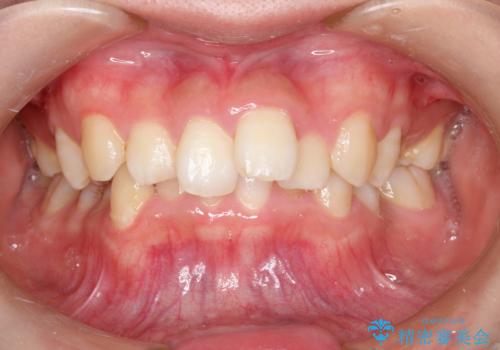

重度のガタガタのインビザラインによる非抜歯矯正

- 全体的なガタガタを気にされて来院されました。

抜歯矯正も考えられる状態でしたが、ご本人的になるべく歯を抜かない矯正を希望されました。

奥歯を後方に移動させるのと、歯と歯の間にわずかに隙間を作ることでスペースを確保して、抜歯をせず歯を並べる計画としました。

ガタガタの度合いが大きかったので少し時間がかかりましたが、非常に協力的な患者様でしたので、抜歯をせず計画通りに治療を終えることができました。